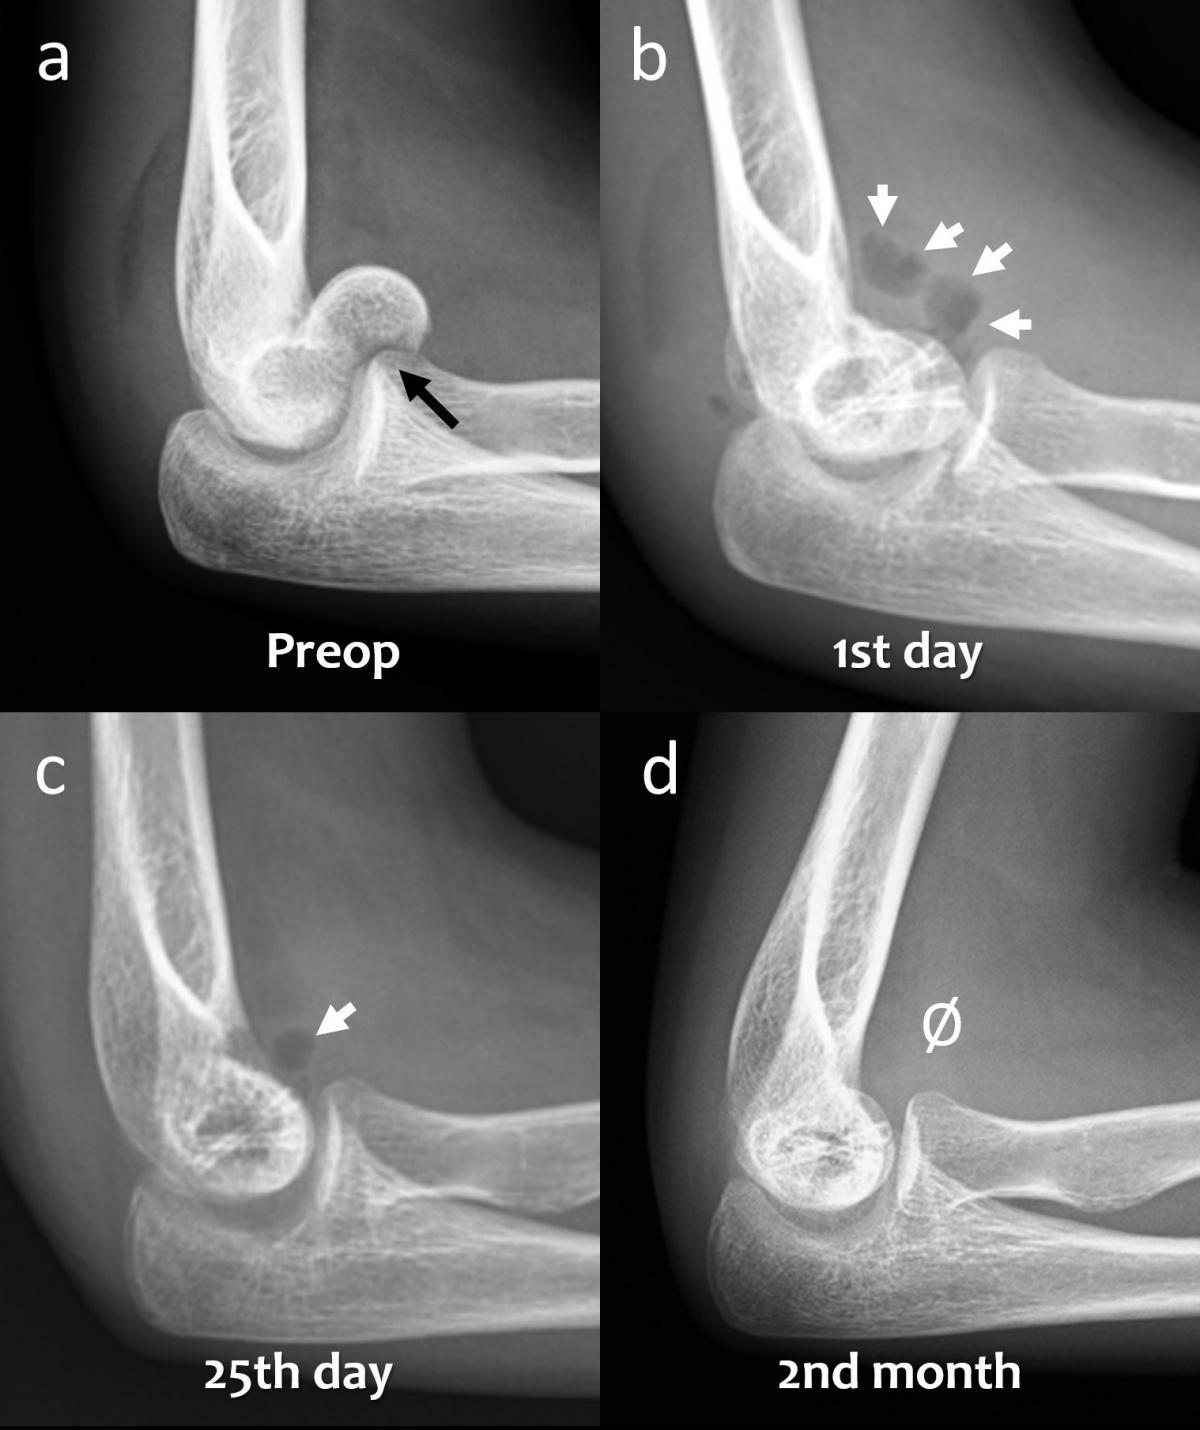

Das konventionelle Röntgenbild wird sowohl für die Diagnose als auch zur Nachbeobachtung bei der Frakturbehandlung verwendet. Häufig beurteilen Chirurgen die Knochenheilung anhand der körperlichen Untersuchung und klinischer Zeichen (wie Schmerzempfindlichkeit, Belastbarkeit und Funktionsfähigkeit) in Kombination mit den radiologischen Befunden (wie Kallusbildung, fehlender Frakturlinie und erfolgter Knochenkonsolidierung). Die radiologische Untersuchung ist also für orthopädische Chirurgen von herausragender Bedeutung [15]. Magnesiumbasierte Implantate zeigen indes ungewohnte radiographische Befunde, die durchaus zu Fehlinterpretationen führen können. Unmittelbar nach der Implantation von Magnesiumschrauben in den Knochen setzt die Degradation über einen Prozess der Korrosion ein. Die Wechselwirkung zwischen Mg und Körperflüssigkeiten führt u.a. zur Bildung von Magnesium-Hydroxid (MgOH) und H2-Gas [16]. In frühen postoperativen Röntgenaufnahmen lässt sich auch Gas im Weichgewebe beobachten, das sich in den Gewebeschichten verteilt. Klinisch produziert dieses Gas aber keine wahrnehmbare Krepitation unter der Haut oder ähnliche Symptome. Die Gasschatten im Weichgewebe bilden sich gewöhnlich rasch zurück (Abbildung 3). In frühen postoperativen Röntgenaufnahmen stellt Gas im Weichgewebe oft ein alarmierendes Signal dar, da es – bei herkömmlichen Metallimplantaten – mit gasbildenden anaeroben Infektionen in Verbindung gebracht wird. Die Bildung von Gas während der

Degradation von Mg-Implantaten hat einen vollkommen anderen Hintergrund – es handelt sich weder um eine Lockerung des Implantates noch gar um eine Infektion. Während des Abbauprozesses via Korrosion nimmt die Gasmenge zu und breitet sich im trabekulären Knochenanteil aus. Schließlich wird es jedoch vollständig resorbiert und die Mg-Schrauben zeichnen sich zunehmend prominenter ab (Abbildung 4). Tierstudien haben gezeigt, dass die Schraube schließlich durch kortikalesKnochengewebe ersetzt wird (7).

(schwarzer Pfeil) in der präoperativen lateralen Röntgenaufnahme des

Ellenbogens. (b) Röntgenaufnahme des Ellenbogens mit Gasansammlung

im Weichgewebe (weiße Pfeile) am ersten postoperativen Tag. (c)

Röntgenaufnahme des Ellenbogens 25 Tage nach der Operation, die

Gasmenge hat sich verringert (weißer Pfeil). (d) Bei der radiographischen

Nachbeobachtung nach 2 Monaten ist kein Gas im Weichgewebe

mehr sichtbar.